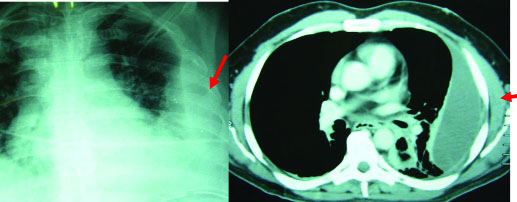

Such patient suffers from fever all the time, but during the daytime fever is less in degree and does increase rapidly during the evening or night-time. Along with the fever, patient complains of excessive sweating all the time. There is a desire to cough but on coughing either nothing or a small amount of phlegm comes out. On coughing patient feels pain in the chest especially on the side of pus collection. If you have suffered from pneumonia infection one month before or you have received previously a chest injury and you find that even after one month of infection or chest injury you are still suffering from cough and fever, do not sit idle and immediately get the chest x-ray done. in standing position. This will confirm the diagnosis of pus in chest is almost 95% case. There are two advantages of doing chest ultrasound examination, firstly it will confirm the presence of pus or water inside the chest cavity and secondly it will quantify the amount of pus collected therein, so that the correct strategy of treatment can be formulated.

There is an empty space between chest wall and lung. When we breathe lung expands and fills up completely this empty space. This empty space in medical terms is called ‘pleural space’. When due to any reason this empty space gets filled up with pus, this condition in medical terms is called ‘Empyema thoracic’. Empyema thoracics simply means in common man’s language a collection of pus around the lung inside the chest.